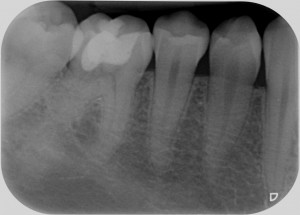

Sì, perchè ora faccio il figo, ma nel non lontano 2011, mi arriva una paziente con questo dente.

Cosa caspita era capitato a questo dente? Allarmato faccio vedere la radiografia a Federico, il mio socio, e anche lui pensa a qualcosa di brutto. Che so, un tumore di quelli incomprensibili che avevamo studiato solo sui libri di radiologia che si era insinuato all’interno di questo 4.6! ???

Quando nel 2013 mi è arrivato all’attenzione questo caso

Allora per capirci qualcosa in più ho fatto una cone beam.